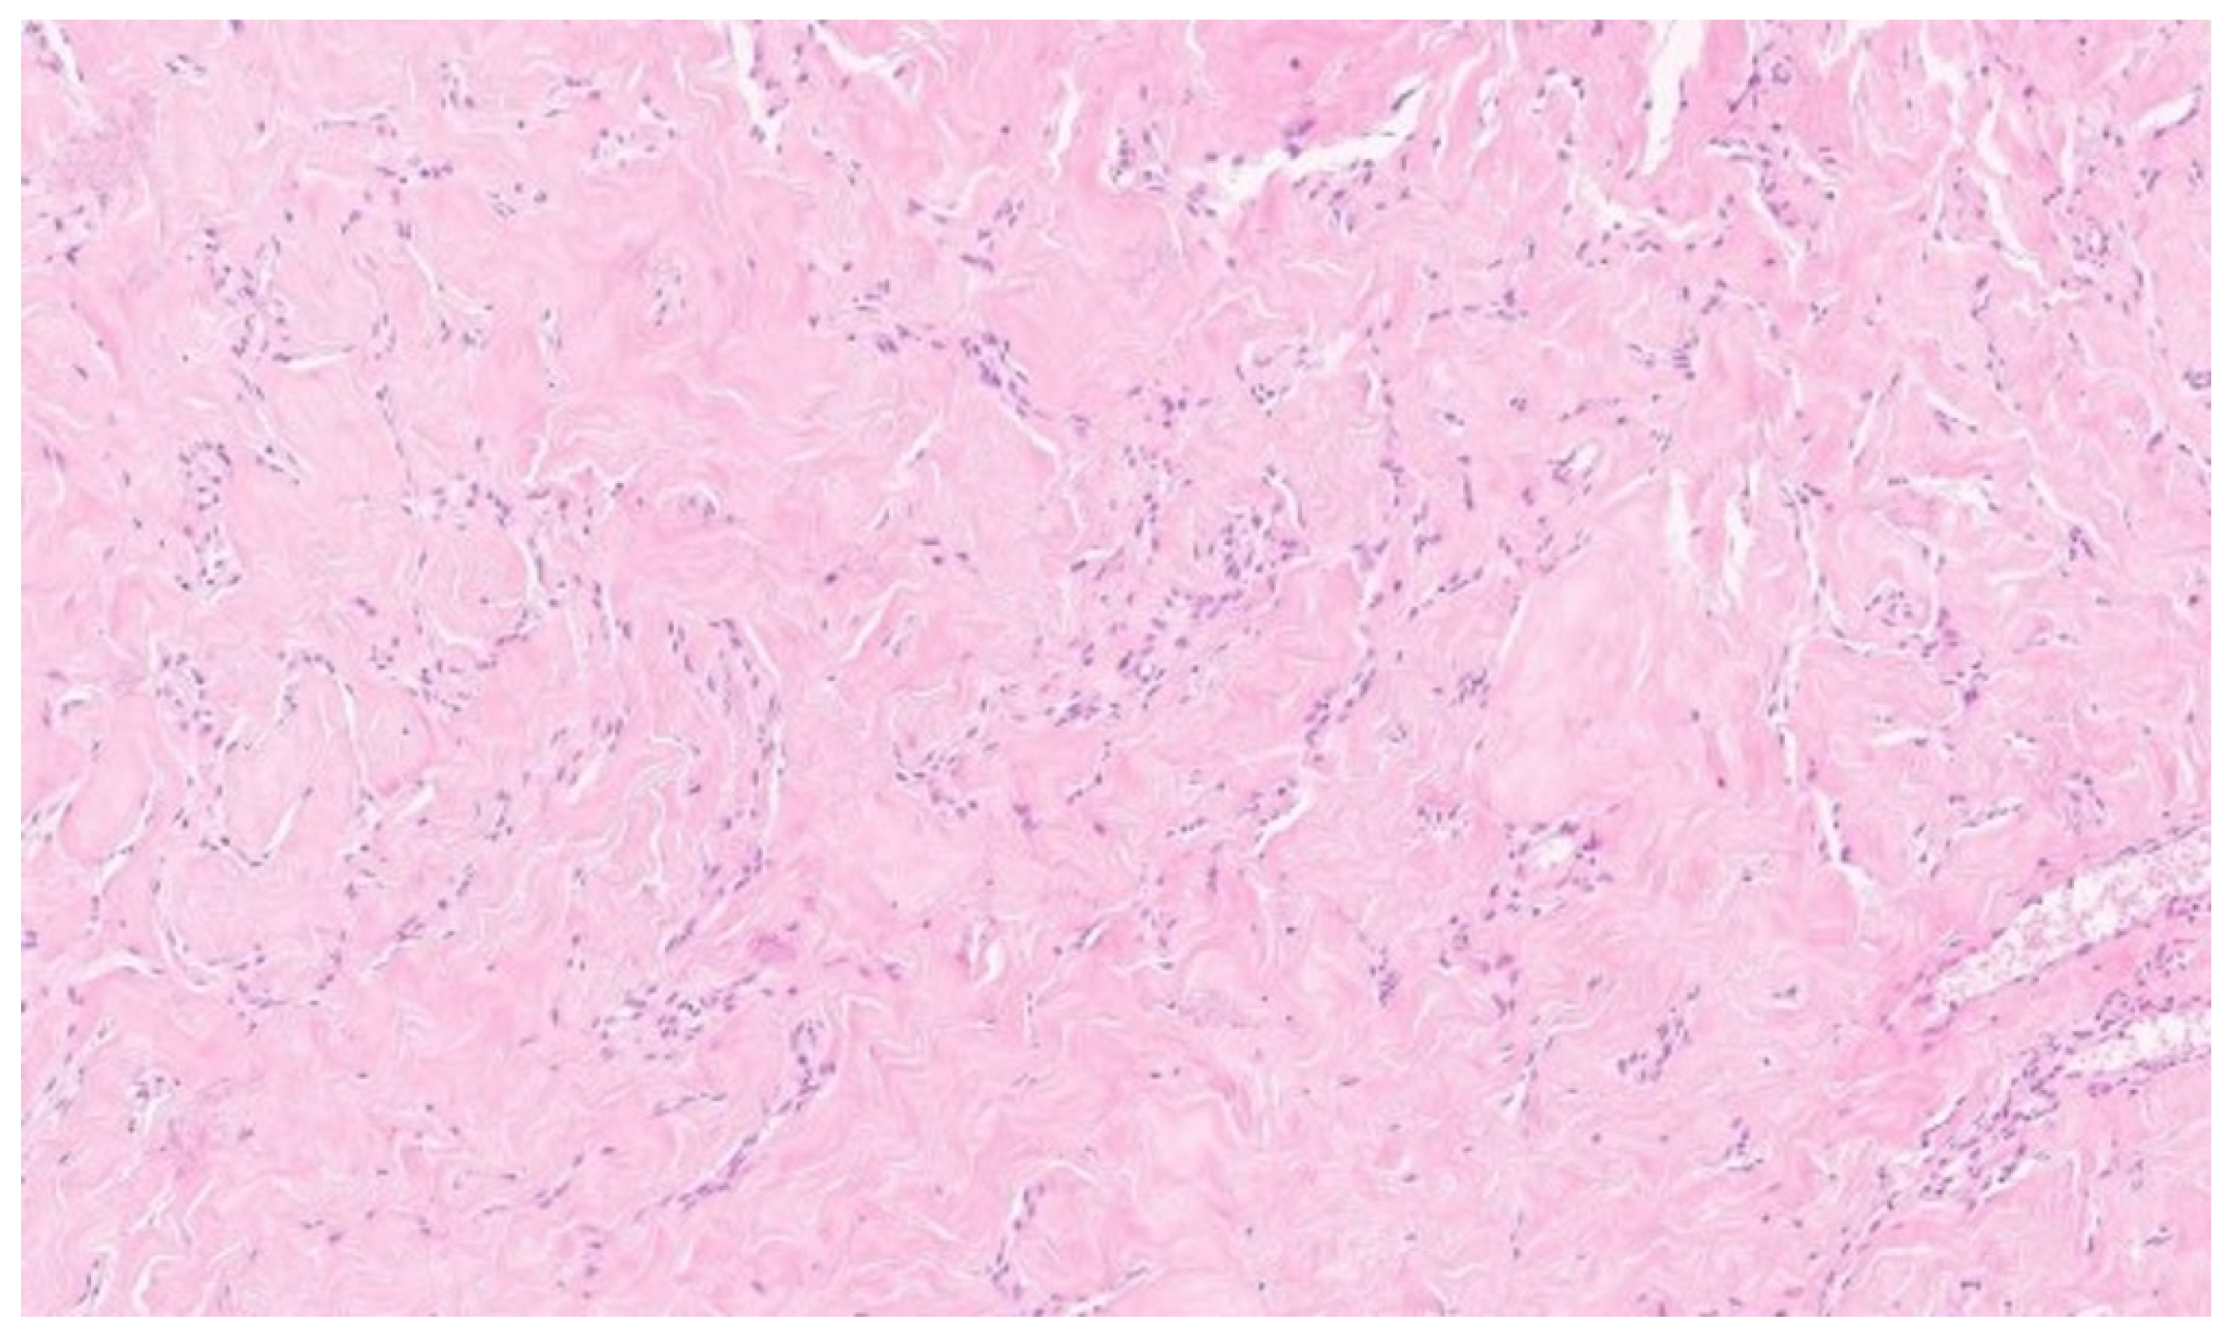

The histopathological examination confirmed the diagnosis of pseudoangiomatous stromal hyperplasia (PASH). The specimen was described as a solid, light gray-to-yellow tumor measuring 11 × 10 × 4.8 cm3, with the capsule preserved and intact (Figure 2 and Figure 3).

On gross examination, PASH typically appears as a well-circumscribed and encapsulated breast lesion, occasionally presenting in a diffuse form. The cut surface is smooth, firm, or rubbery, glistening, and varies in color from gray to tan-pink, yellow, or white [4]. In our patient, the lesion was described as a solid, light gray–yellow mass.

Microscopically, the hallmark of PASH is the presence of slit-like spaces resembling vascular channels, lined by spindle cells, without endothelial markers (CD31–), but with positive CD34 expression, which was also confirmed in our case [4,16].

Figure 3. Histological images of the PASH. Multiple interconnected slit-like pseudoangiomatous spaces, lined by spindle-shaped cells and separated by thick, hyalinized collagen bundles. H and E, 10×.